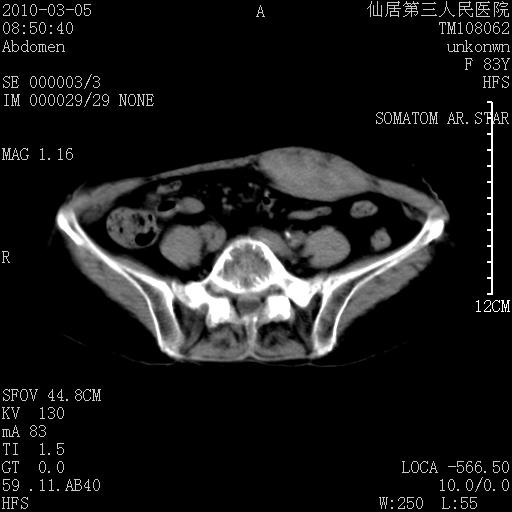

标题: CT24879:腹直肌病变。在线等。 [打印本页]

标题: CT24879:腹直肌病变。在线等。

女性,83y,腹痛一周。

考虑:左侧腹直肌神经纤维瘤可能

神经纤维瘤—伴有出血?

有无外伤,血肿或韧带样瘤

考虑左侧腹直肌血肿,肿瘤性病变待排。

增强看看,mfh可能性大,次之可考虑血肿、bfh、转移瘤、神经纤维瘤、侵袭性韧带样纤维瘤等。肝内钙化灶,右肾结石。

血肿,纤维瘤,子宫内膜异位都有可能。